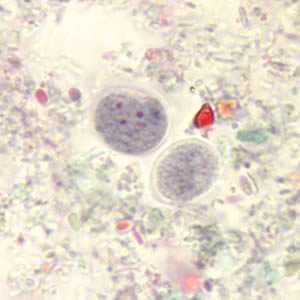

Endolimax nana

Endolimax nana cysts in concentrated wet mounts.

Figure A: Cysts of E. nana stained with trichrome.

Figure B: Cyst of E. nana stained with trichrome.

Figure C: Cyst of E. nana stained with trichrome.

Figure D: Cyst of E. nana stained with trichrome.